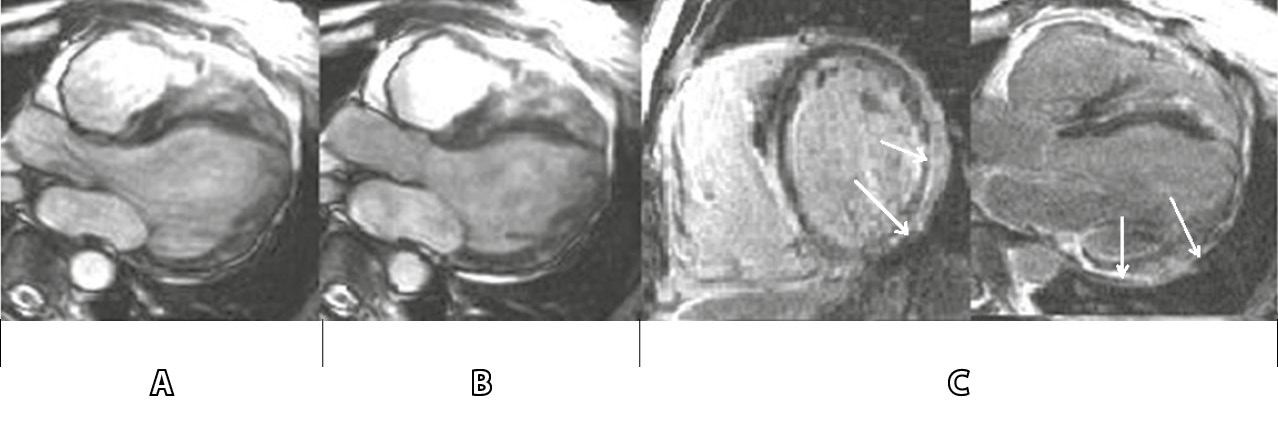

При остром миокардите разрыв мембран кардиомиоцитов позволяет гадолинию диффундировать в клетки, что приводит к повышению концентрации на уровне тканей и последующему усилению контраста. Комбинированный подход МРТ с использованием Т2-взвешенных изображений, раннего усиления сигнала гадолиния и LGE (рис. 2) обеспечивает высокую диагностическую точность и служит полезным инструментом диагностики и оценки пациентов с подозрением на острый миокардит [35, 44].

Рис. 2. Результаты магнитно-резонансной томографии у больного миокардитом (источник – J. Schumm и соавт. [44]): А – диастола, Б – систола, В – позднее усиление гадолиния. Описание: больной жаловался на одышку и боль в грудной клетке. При выполнении магнитно-резонансной томографии сердца выявлены снижение фракции выброса левого желудочка (22%) и эпикардиальная локализация позднего усиления гадолиния (указано стрелками) заднебоковой стенки, что характерно для миокардита. При эндомиокардиальной биопсии: вирусный миокардит, вызванный вирусом герпеса человека 6-го типа. Внезапная сердечная смерть у пациента была зарегистрирована во время наблюдения